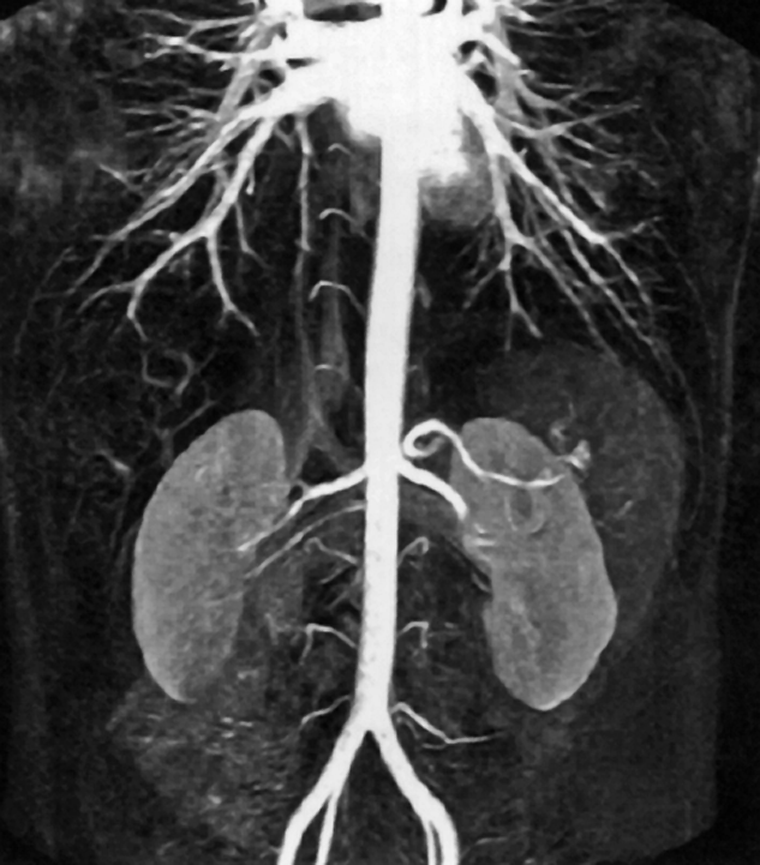

Figura 14-20:

CE-MRA of the abdominal aorta.